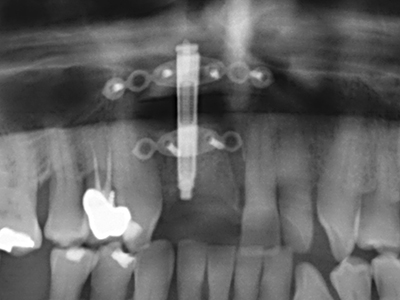

La preparación de la ventana lateral en la elevación del suelo del seno maxilar representa un enorme reto, sobre todo para profesionales de la implantalogía que tienen poca experiencia en técnicas quirúrgicas. Retirar la cobertura ósea del seno maxilar sin provocar daños en la membrana de Schneider es tan solo una parte de la operación; tras crear un acceso suficiente, es preciso movilizar con cuidado la mucosa del seno maxilar a fin de dejar espacio para el material o los implantes que vayan a incorporarse. En esta aplicación la cirugía piezoeléctrica resulta útil en dos sentidos: por un lado, el uso de insertos diamantados permite realizar una retirada selectiva del hueso y, si se actúa con cuidado, la membrana permanece intacta, y por otro lado, las frecuencias de ultrasonidos favorecen también un desprendimiento sin problemas de la membrana, pues se transfieren al espacio comprendido entre la mucosa y el suelo del seno maxilar gracias al uso de piezas romas especiales (Cassetta, Ricci et al. 2012, Pereira, Gealh et al. 2014) (Rickert, Vissink et al. 2013). De este modo, no es de extrañar los trabajos publicados en la actualidad sobre la técnica de elevación del suelo del seno maxilar mediante la técnica de Caldwell-Luc con instrumentos piezoeléctricos (Wallace, Tarnow et al. 2012).

Como ya se ha demostrado en el pasado, básicamente cualquier procedimiento de cirugía de hueso representa una posible indicación para la cirugía piezoeléctrica. Así, la preparación del segmento móvil en la osteogénesis de distracción (fig. 23-25) y en la osteotomía de sándwich puede realizarse con piezas especiales, sin poner en peligro el suministro sanguíneo de la parte crestal, que resulta esencial para el éxito de ambas técnicas (González-García, Diniz-Freitas et al. 2008).

En la cirugía del seno maxilar surgen otros campos de aplicación: En este punto, tras la preparación concéntrica de una tapa ósea de la pared del seno maxilar (que suele tener forma trapezoidal), es posible eliminar patologías y cuerpos extraños del seno maxilar. La tapa ósea se repone después de finalizar la parte intra-antral de la operación y se asegura frente a una posible dislocación mediante cuñas o suturas adaptables.